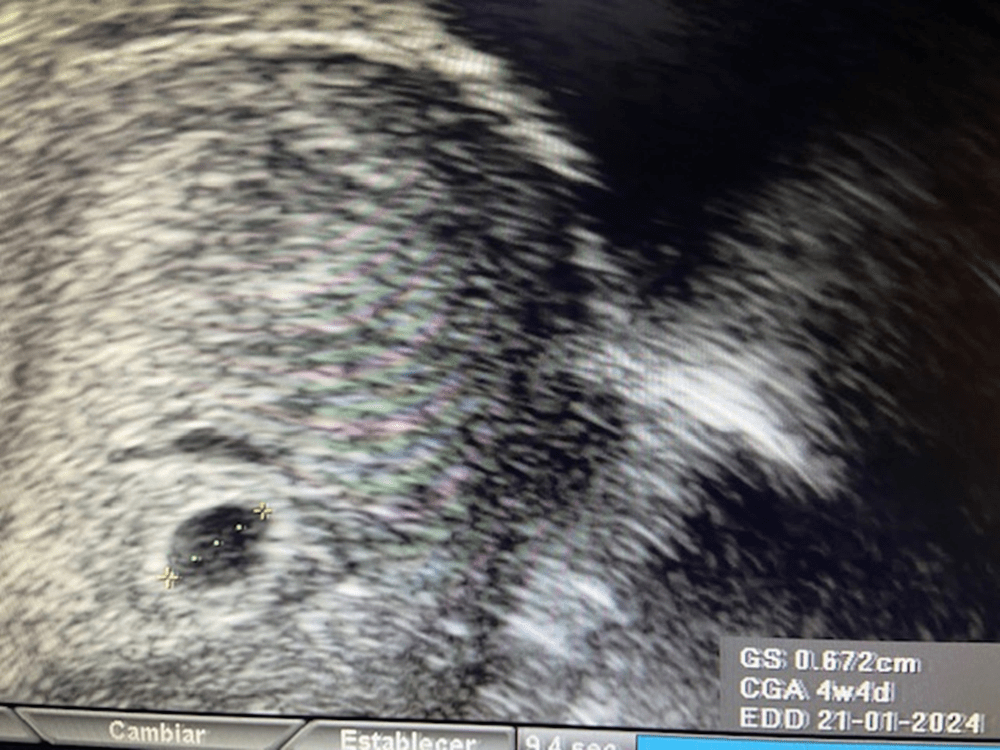

El saco ovular va creciendo rápidamente y 4 días más tarde ya mide 7 mm.

Clínica Ginecológica Dr. Francisco Valdivieso.